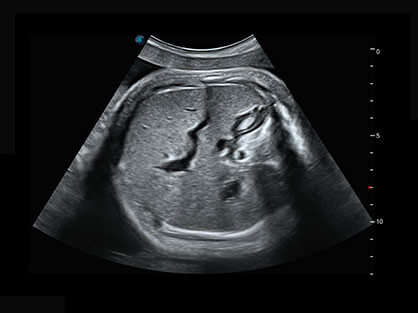

0.5mm厚度的薄层切片显像,可清晰显示微小病灶的连续断面。

可同时显示组织结构表面和内部的轮廓信息,达到透视效果,为临床提供更丰富的诊断信息。